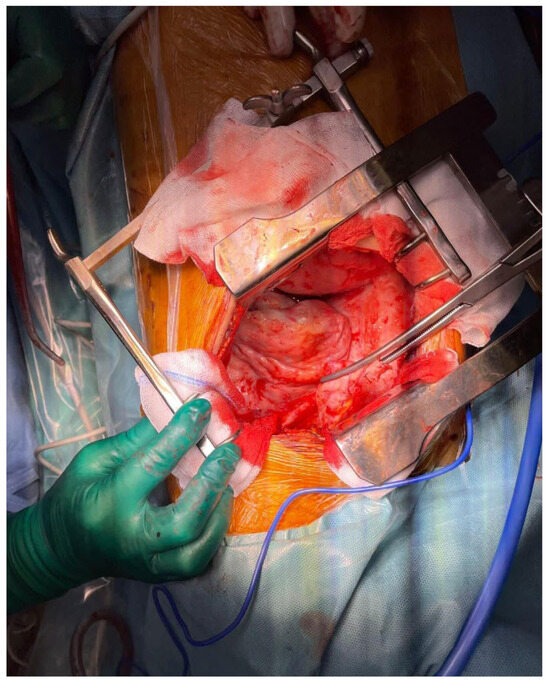

Successful Implementation of HITOC and HIPEC in the Management of Advanced Ovarian Carcinoma with Pleural and Peritoneal Carcinomatosis

Moldovan, B.; Saon, C.T.; Adam, I.-I.; Pisica, R.-M.; Silaghi, V.T.; Untaru, V.; Stoica, D.; Crisan, M.; Popianas, A.; Pescaru, F.; et al. Successful Implementation of HITOC and HIPEC in the Management of Advanced Ovarian Carcinoma with Pleural and Peritoneal Carcinomatosis. Diagnostics 2024, 14, 455. https://doi.org/10.3390/diagnostics14050455